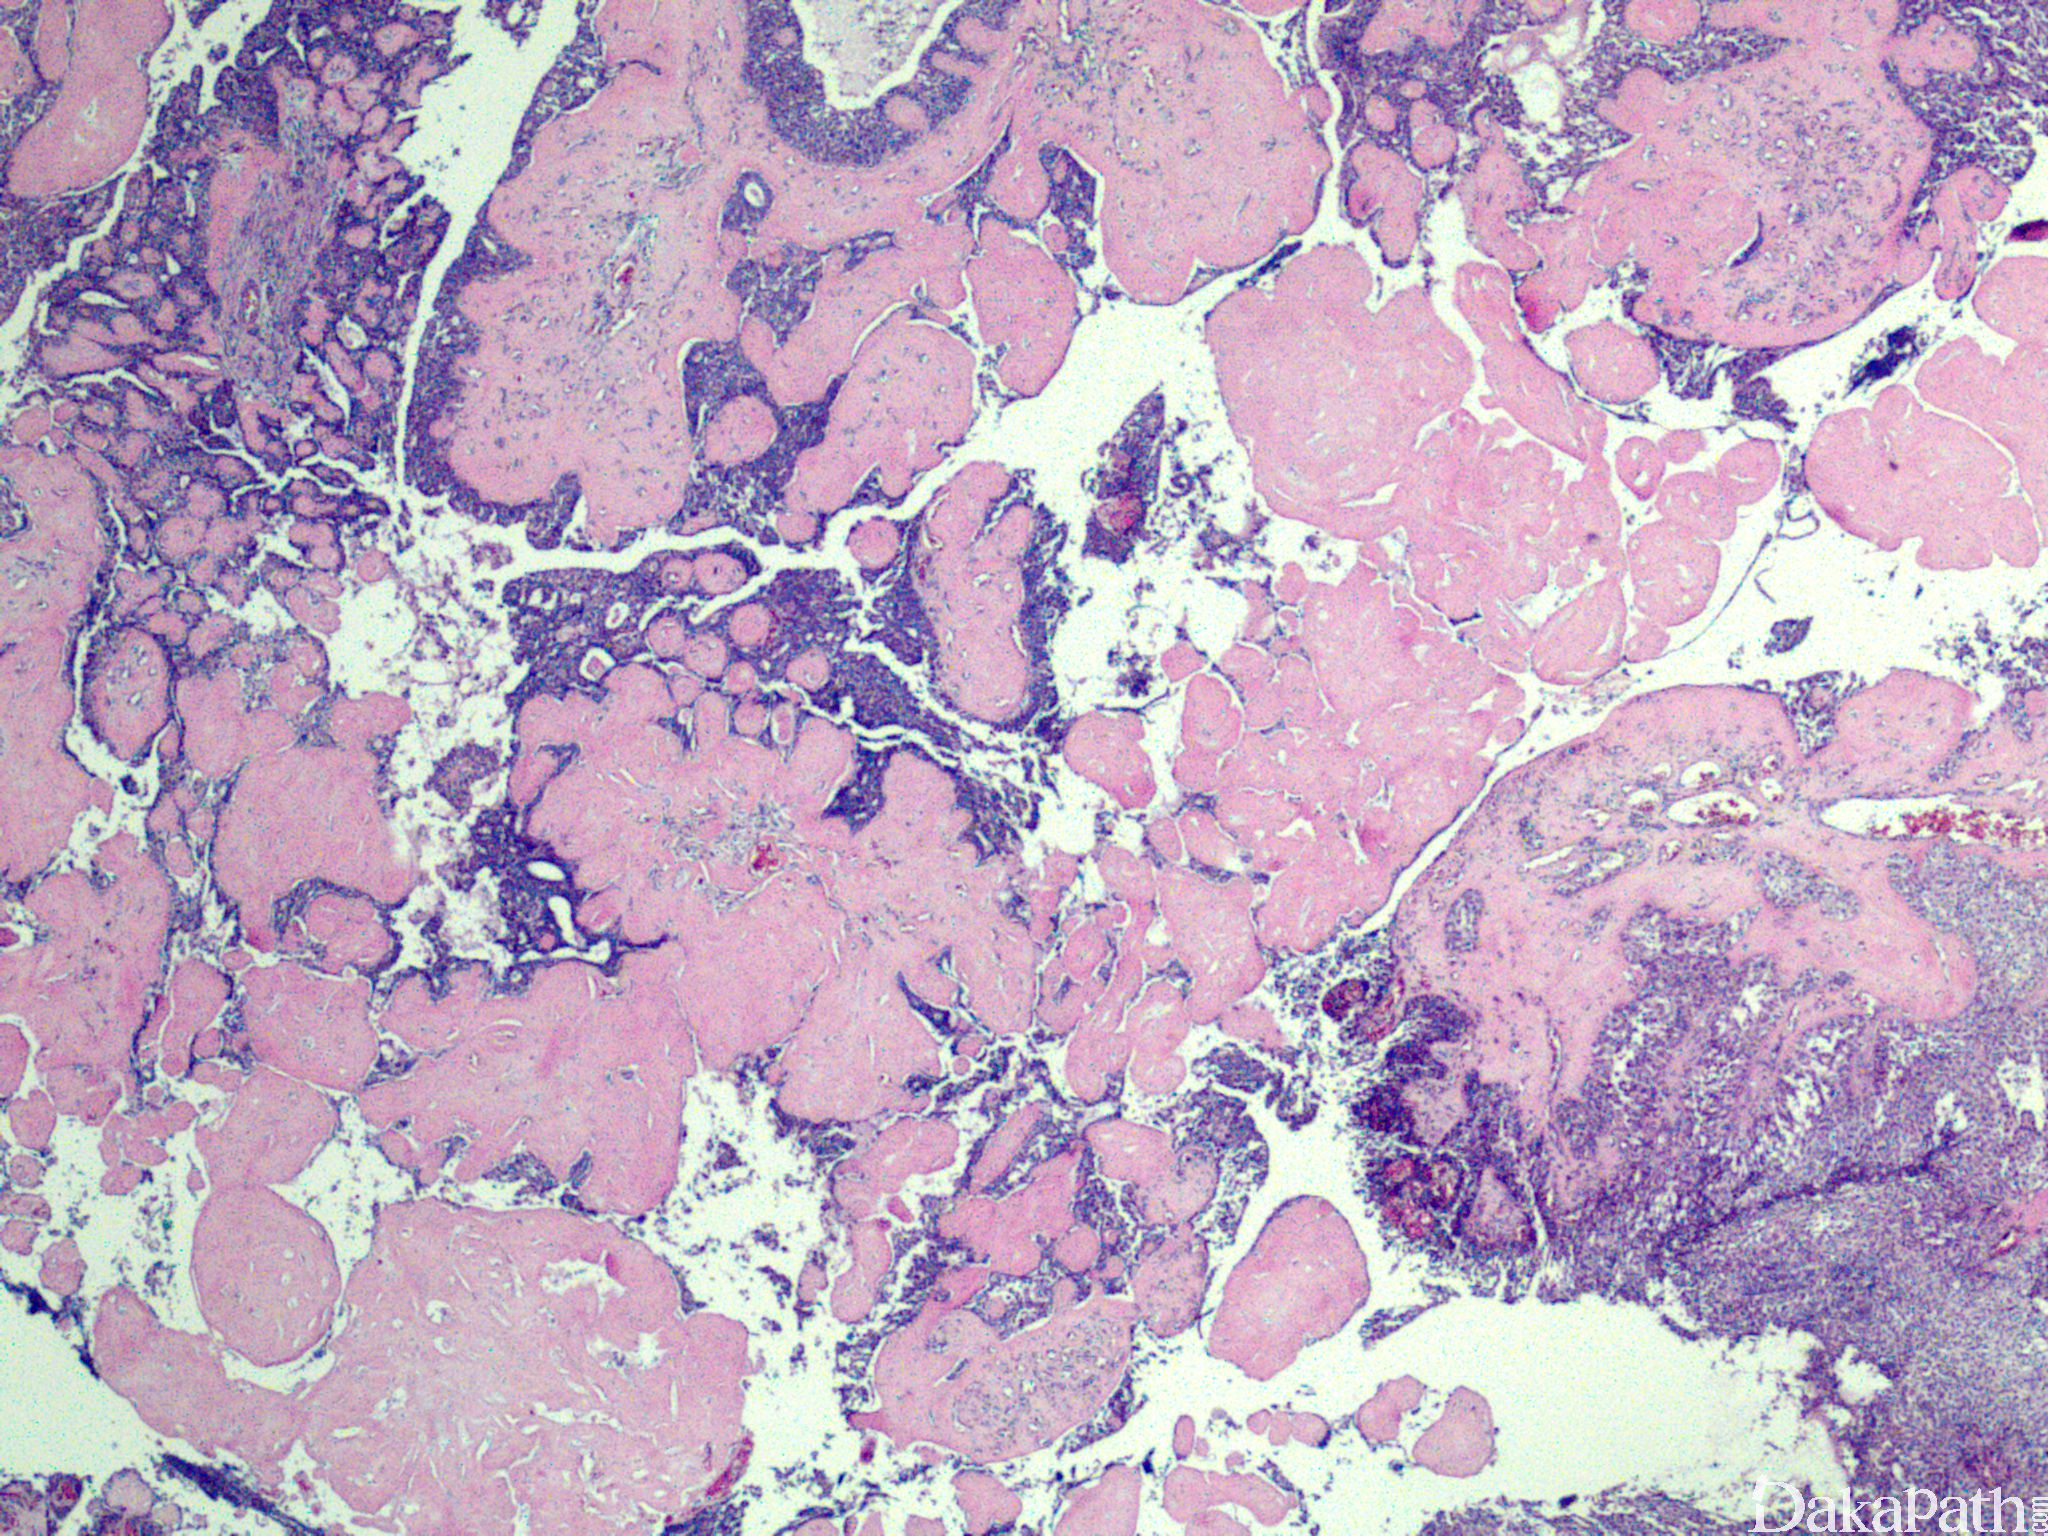

具有典型汗腺瘤形态学特征,呈囊性结节性生长,具透明细胞、鳞样细胞、肌上皮细胞等多种细胞成分;

可见小腺管及上皮细胞内小泡;